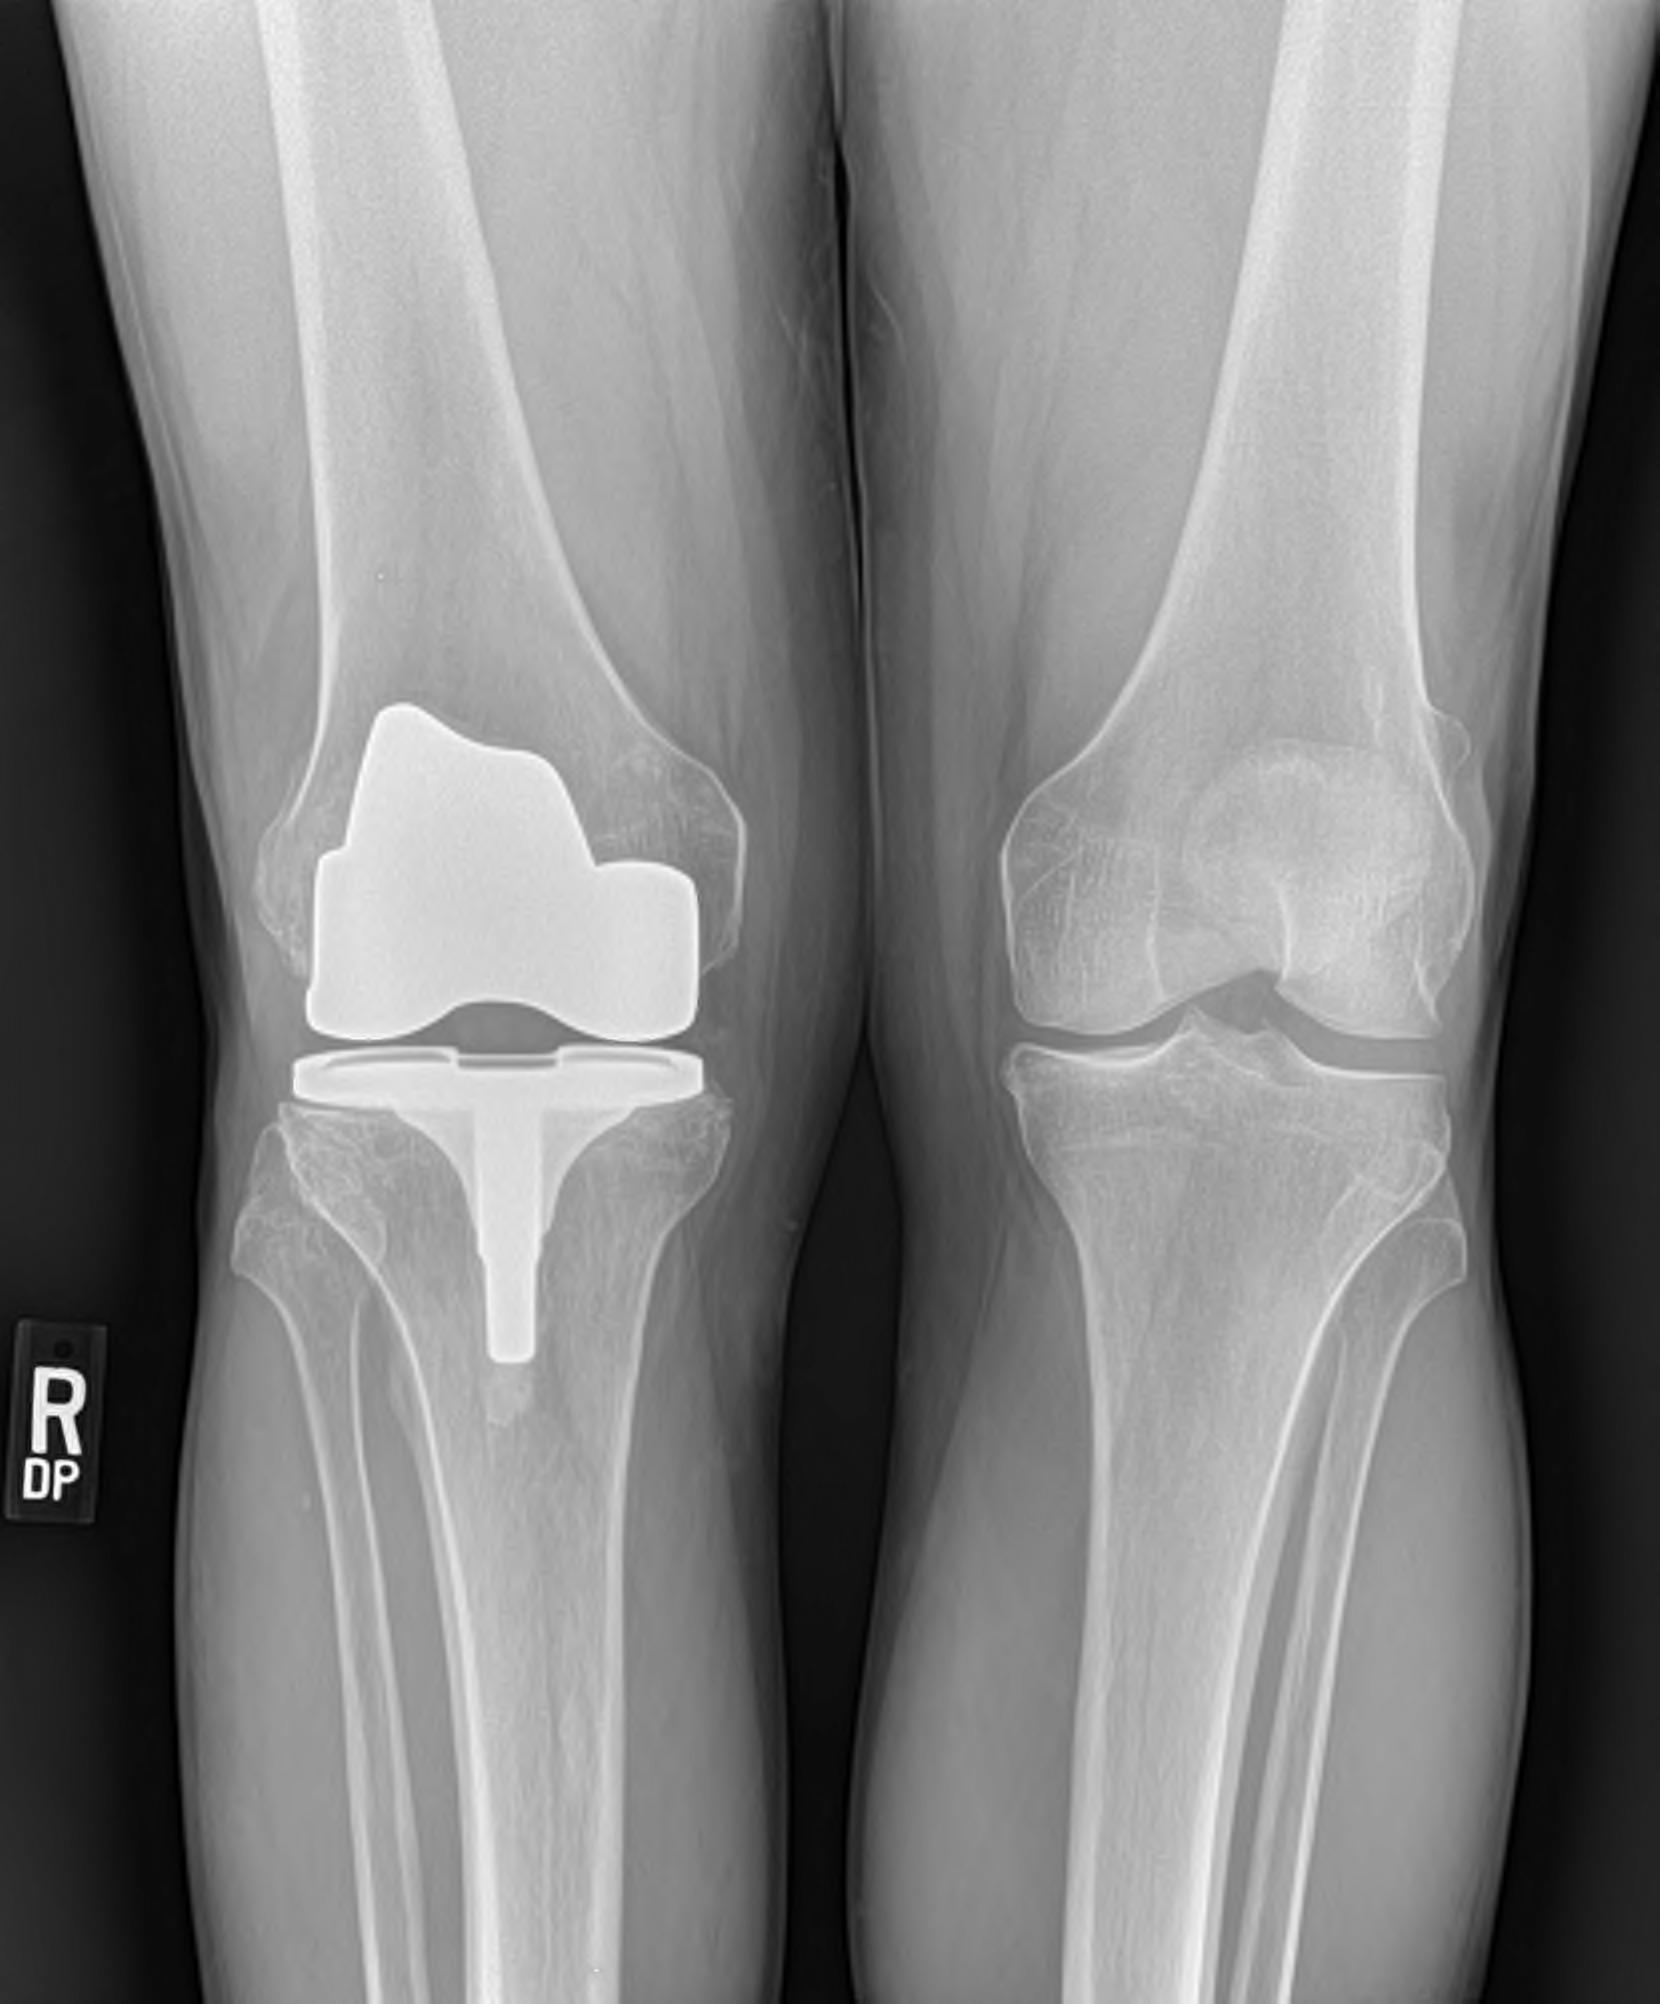

The company ORTHOPEDIC NIKIFOROV was founded in 1998 by the candidate of medical sciences. doctor of orthopedic-traumatologist of the highest category Nikiforov IA Owing to high professionalism and results of work, ORTONIC has gained well-deserved reputation and reputation among colleagues and population of Dnepropetrovsk region and CIS countries (Russia, Moldova, Armenia, etc.). The principle of the enterprise is NO IMPOSSIBLE, it is based on knowledge, experience and active implementation of modern technologies in orthopedics and traumatology. Conservative methods of treatment include individual selection of medicines, therapeutic blockades, manual therapy, massage, physiotherapy (vibration table, magnetotherapy, bioptron, electromyostimulation, etc.), rehabilitation with the suggestion of the necessary concomitant devices and means for the fastest recovery (corsets, bandages, various joint fixators, crutches, walking sticks, etc.). Various minor invasive interventions (chymonucleolysis, vertebroplasty, kyphoplasty, percutaneous nucleoplasty using cold plasma) that are performed on an outpatient basis are successfully used to treat problems associated with spine pathology. The latest modern treatment methods introduced in our company are endoscopic operations using the TYSSES technique of Joimax (Germany) with intervertebral hernias, stenosis and other pathologies of the spine, which allow to avoid complications occurring during open operations and the accompanying general anesthesia. We have many years of successful experience in traditional and modern minimally invasive endoprosthetics of large and small joints, which remains the main direction of our activity. Our company is the exclusive representative of the German company IO International Orthopaedics Holding GmbH, which based on the already known prostheses, its ideas and technological capabilities, has developed and implemented a new concept in hip replacement - an artificial joint prosthesis (ICON). We assist interested colleagues in training the operative technique for installing an artificial joint prosthesis - ICON, both in the workplace and in Germany. For 20 years we have been successfully cooperating with Sanitatshaus Gerd Klinz ortho team, an enterprise that for 20 years has been one of the leading places in Germany for the production of functional prostheses of the upper and lower limbs, as well as cosmetic prostheses of limbs and other body parts (nose, ears, eyeballs, fingers). We have an atmosphere of friendliness and human participation. Politeness, benevolence, the desire to understand and help is the basis of our attitude towards patients. We are always glad to see you and will do our best to make you feel great! We are waiting for you at: Ukraine, Dnepr, Gagarin Ave., 13 (under reconstruction) on all questions to address: tel .: +38 (050) 488-88-92 E-mail: orthonik.ukr@gmail.com Germany, Spine Nano Klinik, Zeppelinstr. 21, Potsdam Tel. +4901801121919 E-mail: kmw.nikiforov@hotmail.de